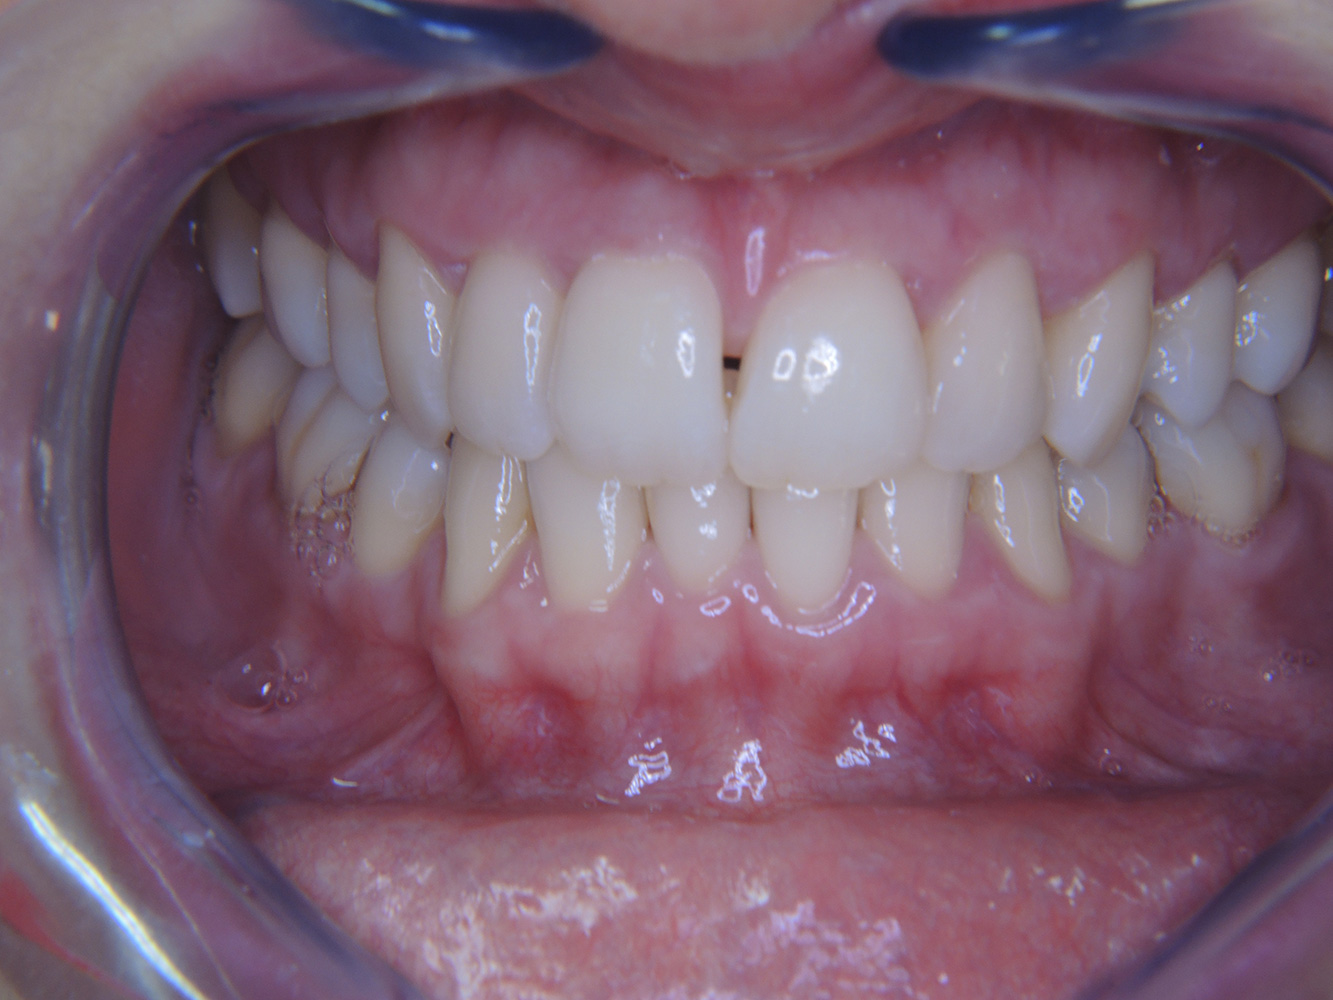

Eine 51-jährige mundgesunde Diabetikerin stellt sich zur Präventionssitzung vor. Die Blutzuckerwerte sind stabil bei einem HbA1c = 6,2%, folglich gilt sie mit dem entsprechenden Medikament Metformin (Antidiabetikum) als suffizient eingestellt. Die Patientin hat keine bestehenden Versorgungen oder orale Vorerkrankungen. Anhand der aktuellen Befunde lässt sich eine Gingivitis bei sonst stabilem parodontalem Zustand (Stage II, Grad B) feststellen.